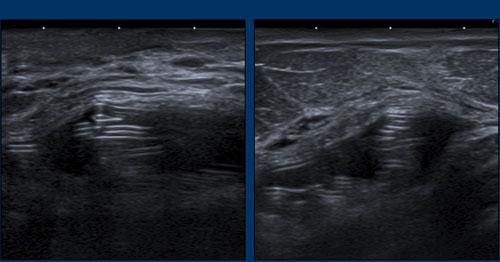

Hình ảnh

Thêm các ví dụ về “dấu hiệu thang”.

Ở bệnh nhân này, vôi hóa bao xơ nặng nề đã che khuất tình trạng của túi độn.

Tuy nhiên, khi quan sát từ một góc độ khác, dấu hiệu thang cho thấy rõ ràng có vỡ túi.

Do vôi hóa lan rộng, không thể xác định chắc chắn liệu đây chỉ là vỡ túi trong bao xơ hay còn kèm theo rò rỉ Silicone ngoài bao xơ.

A. Không còn nhìn thấy vỏ bọc xung quanh bề mặt túi độn. Nội dung bên trong hoàn toàn không đồng nhất và thoái hóa.

B. Vỏ bọc bị xẹp (mũi tên vàng) và không đi theo phức hợp vỏ bọc-bao xơ bên ngoài (mũi tên trắng).

Có một khối tập hợp không đồng nhất chứa Silicone nằm giữa vỏ bọc và bao xơ.